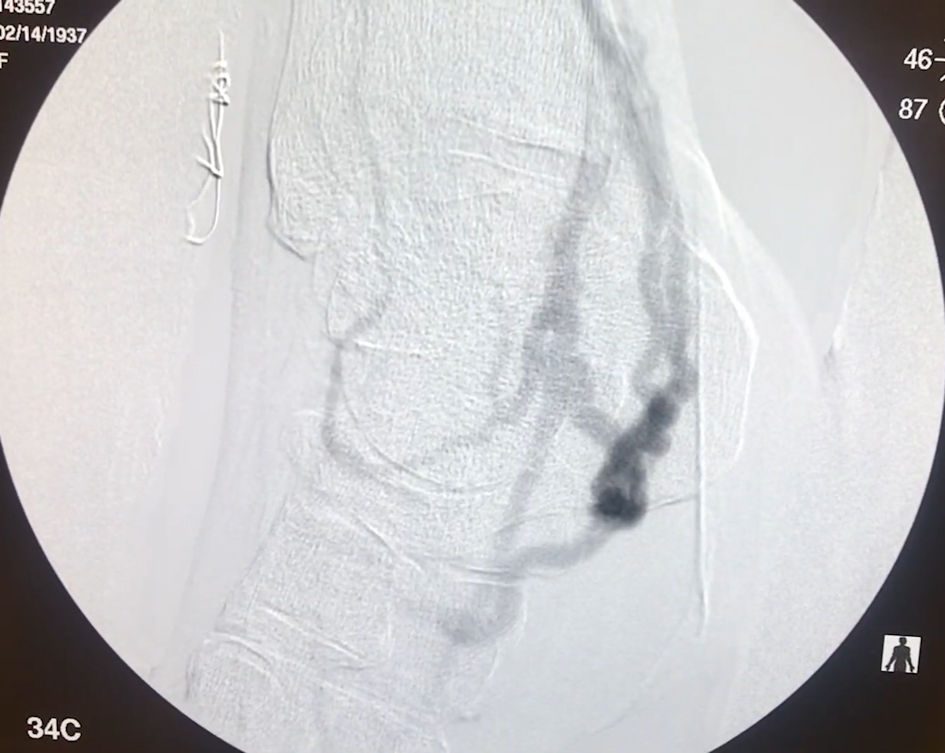

An 80-year-old woman with significant medical comorbidities of coronary artery disease, hypertension, poorly controlled diabetes mellitus, hyperlipidemia, and an over 10 year, one-pack-per-day smoking history, presented to a vascular surgeon with CLTI and dry gangrene of the second toe, who underwent planned common femoral artery (CFA) to posterior tibial artery (PTA) bypass surgery for revascularization. Immediately after surgery, the patient’s pain increased. She developed additional gangrene of her third and fourth toes, a new wound on the dorsum of her foot, and a new wound at the anastomosis site of the bypass (Fig. 1). The patient was offered a below-knee amputation after 2 months, with worsening symptoms. The patient then presented for a second opinion. Angiography demonstrated that the graft was inadvertently anastomosed to the peroneal vein near the foot (Fig. 2). Two additional vascular surgeons both deemed the patient at too high a risk for bypass revision due to her comorbid medical conditions and lack of additional venous conduit. Due to the patient’s deteriorating condition and comorbidities, percutaneous revision of the bypass was offered.

Click for large image

Figure 1. Right foot at initial presentation with new gangrene involving the third and fourth toes, a new wound on the dorsum of the foot.

Figure 2. Angiography of the lower leg and foot was performed prior to the revision. The peroneal vein was arterialized by the bypass graft, with diminished blood flow to the forefoot.